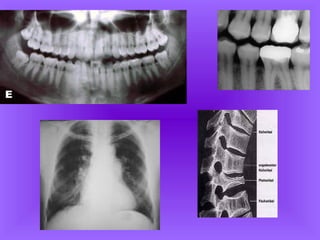

O que é uma radiografia?

Radiografia é uma gravação fotográfica

visível, em filme, produzida pela passagem

de raios X através de um objeto ou corpo. A

radiografia torna possível estudar as

estruturas internas do corpo como auxiliar

de diagnóstico

Os raios X ondas eletromagnéticas muito

energéticas, de modo que podem penetrar

muitos materiais e em graus variáveis. Como

o osso, a gordura, os músculos, os tumores

e outras massas absorvem os raios X em

níveis diferentes e, conseqüentemente,

promovem níveis de exposição diferentes no

filme. A imagem gerada permite que você

veja estruturas distintas dentro do corpo